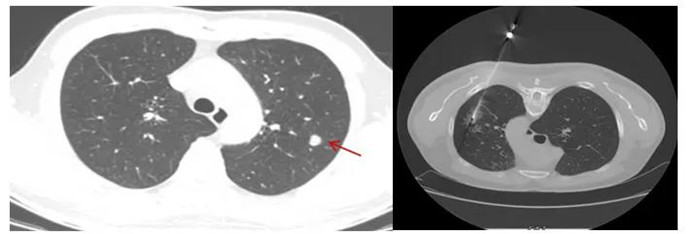

CT引導下肺穿刺活檢,8毫米肺結(jié)節(jié)排除肺癌可能

黃先生肺結(jié)節(jié)的性質(zhì)變得難以確定,經(jīng)評估,金旭如帶領呼吸介入團隊給黃先生行肺穿刺活檢。

“通過CT掃描測量,確定穿刺進針點、方向、距離,使用肺穿刺針經(jīng)胸壁穿刺到肺結(jié)節(jié)部位,進行3~4次切割取材,獲取組織送檢驗及病理切片?!睉c幸的是,穿刺結(jié)果顯示,黃先生的肺結(jié)節(jié)為:肺隱球菌病。

CT定位下經(jīng)皮肺穿刺活檢

行CT引導下經(jīng)皮肺穿刺活檢術(shù)前,患者需要排除近期服用抗凝藥物、自身凝血障礙等禁忌癥,術(shù)前完善CT增強掃描,以顯示肺結(jié)節(jié)與周圍血管分布的關(guān)系,明確穿刺時的位置選取,最大程度避免傷及血管,減少出血風險。